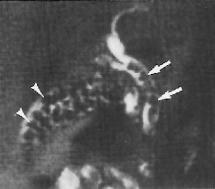

Choledocholithiasis and cholelithiasis. Ultrasound (not shown) revealed GB stones and bile duct dilatation but no bile duct stones. MR cholangiogram demonstrates multiple stones in both the gallbladder (arrowheads) and in the dilated extrahepatic bile duct (arrows).